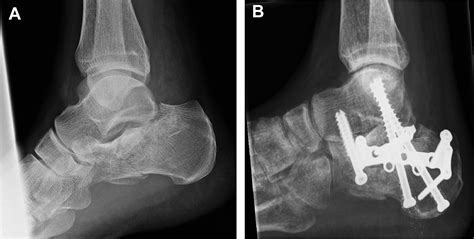

• Bone Preparation: The cartilage and any damaged bone are removed from the joint surfaces to prepare them for fusion.

• Bone Grafting: In some cases, bone grafts may be used to promote healing and fusion. These grafts can be taken from the patient's own body or from a donor.

• Fixation: The bones are aligned and held in place using screws, plates, or rods. These fixation devices provide stability while the bones heal and fuse together.